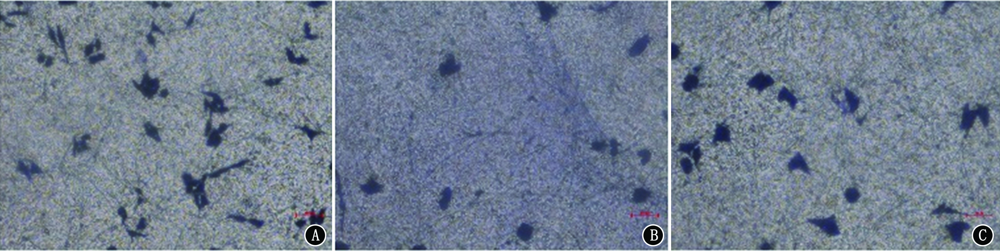

目的 探讨含溴结合域蛋白4(BRD4)抑制剂对野生型Kras分化型甲状腺癌(DTC)的影响及其机制。方法 选取DTC细胞株KrasWT TPC-1,构建基因突变型KrasG12D TPC-1细胞。采用CCK-8法检测BRD4抑制剂JQ-1对KrasWT TPC-1细胞增殖活力的影响。用0.2 μmol/L JQ-1处理Kras WT TPC-1细胞(JQ-1组),另设阴性对照(NC)组,分别采用Transwell侵袭实验、流式细胞术检测JQ-1对KrasWT TPC-1细胞侵袭和凋亡的影响;检测JQ-1对BRD4、miR-106b-5p、P21表达的影响,以及P21抑制剂UC2288对P21、BRD4表达的影响。将KrasWT TPC-1细胞分为JQ-1+NC-OE组、JQ-1+p21-OE组(过表达p21)及JQ-1+p21-OE+miR-106b-5p mimic组(同时过表达p21和miR-106b-5),检测各组细胞增殖、侵袭及凋亡情况。将TPC-1细胞分为KrasWT组、KrasWT+JQ-1组、KrasG12D组及KrasG12D+JQ-1组,检测各组细胞增殖、侵袭及凋亡情况。结果 JQ-1以剂量和时间依赖方式抑制KrasWT TPC-1细胞的增殖活力。在NC组和JQ-1组中,细胞侵袭数分别为124.67±9.61、82.67±8.02,细胞凋亡率分别为(5.91±0.34)%、(10.33±1.10)%,差异均具有统计学意义(t=5.812,P=0.004;t=6.653,P=0.003)。JQ-1显著抑制KrasWT TPC-1细胞中BRD4及miR-106b-5p的表达并促进P21的表达。UC2288显著抑制P21表达,但对BRD4表达无显著影响。JQ-1+NC-OE组、JQ-1+p21-OE组及JQ-1+p21-OE+miR-106b-5p mimic组中,KrasWT TPC-1细胞24 h增殖活力分别为0.46±0.03、0.35±0.04、0.44±0.03(F=8.720,P=0.017),JQ-1+p21-OE组较JQ-1+NC-OE组显著降低(P<0.05);3组细胞侵袭数分别为83.00±9.17、56.67±6.03、79.67±10.07(F=8.347,P=0.018),JQ-1+p21-OE组较JQ-1+NC-OE组显著减少(P=0.009);3组细胞凋亡率分别为(10.00±0.49)%、(15.39±1.14)%、(10.32±0.80)%(F=37.764,P<0.001),JQ-1+p21-OE组较JQ-1+NC-OE组显著增加(P<0.001);JQ-1+p21-OE+miR-106b-5p mimic组与JQ-1+NC-OE相比,细胞增殖活力、侵袭数及凋亡率差异均无统计学意义(均P>0.05)。在KrasWT组、KrasWT+JQ-1组、KrasG12D组及KrasG12D+JQ-1组中,24 h细胞增殖活力分别为0.50±0.05、0.39±0.04、0.68±0.08、0.64±0.05(F=17.776,P<0.001),与KrasWT组相比,KrasWT+JQ-1组增殖活力显著降低,KrasG12D组增殖活力显著升高(均P<0.05);各组细胞侵袭数分别为129.33±11.50、86.00±9.54、161.67±13.01、146.33±13.20(F=22.598,P<0.001),与KrasWT组相比,KrasWT+JQ-1组侵袭数显著降低(P=0.002),KrasG12D组侵袭数显著增加(P=0.010);各组细胞凋亡率分别为(6.17±0.50)%、(10.42±0.73)%、(3.43±0.47)%、(3.41±0.32)%(F=119.170,P<0.001),与KrasWT组相比,KrasWT+JQ-1组中细胞凋亡率显著增加(P<0.001),KrasG12D组凋亡率显著降低(P<0.001);KrasG12D+JQ-1组细胞增殖活力、侵袭数及凋亡率与KrasG12D组相比差异均无统计学意义(均P>0.05)。结论 BRD4抑制剂能够通过调节BRD4/miR-106b-5p/P21分子轴,特异性抑制Kras野生型DTC的发展,而对Kras突变型DTC肿瘤细胞的增殖、侵袭和凋亡无显著影响。

Objective To explore the influence of bromodomain-containing protein 4 (BRD4) inhibitor on wild-type Kras differentiated thyroid carcinoma (DTC) and its mechanism.Methods The DTC cell line KrasWT TPC-1 was selected and the mutant KrasG12D TPC-1 cells were constructed. CCK-8 assay was used to detect the effect of BRD4 inhibitor JQ-1 on the proliferation activity of KrasWT TPC-1 cells. KrasWT TPC-1 cells were treated with 0.2 μmol/L JQ-1 (JQ-1 group), and a negative control group (NC group) was set. Transwell invasion assay and flow cytometry were used to detect the effect of JQ-1 on the invasion and apoptosis of Kras WT TPC-1 cells. The effect of JQ-1 on the expressions of BRD4, miR-106b-5p and P21, and the effect of P21 inhibitor UC2288 on the expressions of P21 and BRD4 were detected. KrasWT TPC-1 cells were divided into JQ-1+NC-OE group, JQ-1+p21-OE group (overexpression of p21) and JQ-1+p21-OE+miR-106b-5p mimic group (overexpression of p21 and miR-106b-5 at the same time), and the proliferation, invasion and apoptosis of cells in each group were detected. TPC-1 cells were divided into KrasWT group, KrasWT+JQ-1 group, KrasG12D group and KrasG12D+JQ-1 group, and the cell proliferation, invasion and apoptosis of each group were detected. Results JQ-1 inhibited the proliferation activity of KrasWT TPC-1 cells in a dose-dependent and time-dependent manner. In the NC group and JQ-1 group, the numbers of cell invasion were 124.67±9.61 and 82.67±8.02, and the apoptosis rates were (5.91±0.34)% and (10.33±1.10)%, respectively, with statistically significant differences (t=5.812, P=0.004; t=6.653, P=0.003). JQ-1 significantly inhibited the expressions of BRD4 and miR-106b-5p, and promoted the expression of P21 in KrasWT TPC-1 cells. UC2288 significantly inhibited P21 expression, but had no significant effect on BRD4 expression. In the JQ-1+NC-OE group, JQ-1+p21-OE group and JQ-1+p21-OE+miR-106b-5p mimic group, the proliferation activities at 24 h of KrasWT TPC-1 cells was 0.46±0.03, 0.35±0.04 and 0.44±0.03 (F=8.720, P=0.017), and the proliferation activity of JQ-1+p21-OE group was significantly lower than that of the JQ-1+NC-OE group (P<0.05). The numbers of cell invasion in the three groups were 83.00±9.17, 56.67±6.03 and 79.67±10.07 (F=8.347, P=0.018), and the number of cell invasion in the JQ-1+p21-OE group was significantly lower than that in the JQ-1+NC-OE group (P=0.009). The apoptosis rates of the three groups were (10.00±0.49)%, (15.39±1.14)% and (10.32±0.80)% (F=37.764, P<0.001), and the apoptosis rate of the JQ-1+p21-OE group was significantly higher than that in the JQ-1+NC-OE group (P<0.001). There were no significant differences in cell proliferation activity, invasion number and apoptosis rate between JQ-1+p21-OE+miR-106b-5p mimic group and JQ-1+NC-OE group (all P>0.05). In KrasWT group, KrasWT+JQ-1 group, KrasG12D group and KrasG12D+JQ-1 group, the cell proliferation activities at 24 h were 0.50±0.05, 0.39±0.04, 0.68±0.08 and 0.64±0.05 (F=17.776, P<0.001). Compared with the KrasWT group, cell proliferation activity in the KrasWT+JQ-1 group was significantly decreased, while that in the KrasG12D group was significantly increased (both P<0.05). The numbers of cell invasion in the four groups were 129.33±11.50, 86.00±9.54, 161.67±13.01 and 146.33±13.20 (F=22.598, P<0.001). Compared with the Kras WT group, the number of cell invasion in the KrasWT+JQ-1 group was significantly decreased (P=0.002), and that in the KrasG12D group was significantly increased (P=0.010). The apoptosis rates in the four groups were (6.17±0.50)%, (10.42±0.73)%, (3.43±0.47)% and (3.41±0.32)% (F=119.170, P<0.001). Compared with the KrasWT group, the apoptosis rate in the KrasWT+JQ-1 group was significantly increased (P<0.001), and that in the KrasG12D group was significantly decreased (P<0.001). There were no significant differences in cell proliferation activity, invasion number and apoptosis rate between KrasG12D+JQ-1 group and KrasG12D group (all P>0.05). Conclusion BRD4 inhibitor can specifically inhibit the development of wild-type Kras DTC via regulating the molecular axis of BRD4/miR-106b-5p/P21, but has no significant effect on the proliferation, invasion and apoptosis of mutant Kras DTC tumor cells.